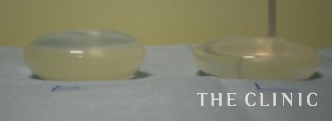

抜去したバッグです。

右と左のバッグの大きさが違いました。

生食バッグの破損はなかったので左右大きさの違うバッグが入っていたと思われます。